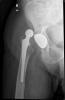

Fractura cuello fémur. Prótesis completa.

Fractura de fémur, prótesis parcial de cadera

Prótesis parcial de cadera

Prótesis de cadera.